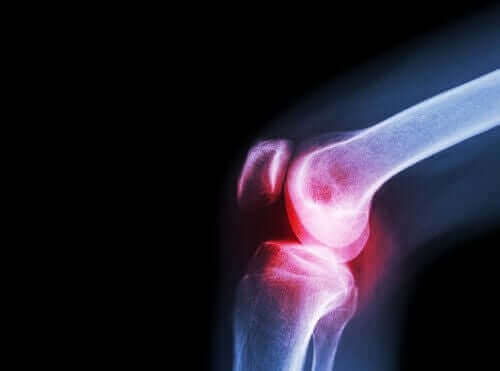

Romatoid artrit, bir kronik enflamatuvar otoimmün hastalığıdır. Bu hastalık çeşitli eklemleri etkiler ve çeşitli genel ve spesifik olmayan belirtileri vardır.

Bu durum düzgün bir şekilde tedavi edilmezse, önemli fiziksel kısıtlamalara neden olarak hastanın hayat kalitesini fark edilir ölçüde kötüleştirebilir.

Semptomlara gelince, romatoid artrit tipik olarak ağrı ve rijitlikle kendini belli eder. Ayrıca farklı küçük ve büyük eklemleri hareket ettirmede de zorluk görülür.

Osteoartrit

Doktorlar bu durum için de aseklofenak önerirler. Osteoartrit, eklem kıkırdağına hasar veren bir başka romatizmalı hastalıktır.

Eklemlerde, sinovyal zar tarafından üretilen sinovyal sıvı isimli bir sıvı bulunur. Bir eklemi oluşturmak için bir araya gelen kemik uçları eklemsel kıkırdak ile kaplıdırlar.

Bu kıkırdakta hasar oluştuğunda, bu hasar, ağrıya, katılaşmaya ve fonksiyonel yetersizliğe yol açar. Bu nedenle, bu hastalığı artritten ayırt etmek önemlidir. İkinci hastalık, kıkırdak yıpranması nedeniyle değil enflamasyon nedeniyle gelişir.